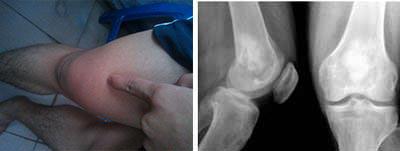

(图:患者治疗前膝关节红肿)

T37℃,P80次/分,R20次/分,BP110/80KPa,巩膜无黄染,浅表淋巴结不肿,无颈静脉充盈,双肺呼吸音清,心律齐,下膝关节疼痛,肘关节疼痛,膝关节红肿明显,脊柱四肢无畸形。

类风湿因子60 IU/ml,抗链球菌溶血素287.1u/ml,血沉20mm/h,超敏C反应蛋白19mg/L。

赵先生长期生活在潮湿生活环境中,2011年9月,出现双膝关节游走性疼痛症状,自行买来止痛药服用后,疼痛缓解。但是快速阴雨天时,关节疼痛再次发作,且遇冷关节发僵发白,疼痛无比。吃止痛药无效后,去医院检查,医生诊断为风湿性关节炎。接受药物治疗三年,膝关节出现红肿现象,关节屈伸不利,食欲下降,晨起关节僵硬持续一小时。2014年8月,多方打听后,来到我院求助陈建春主任。